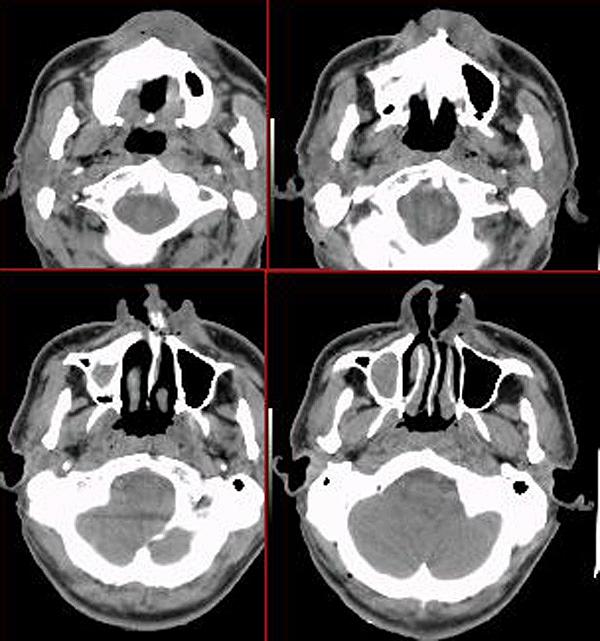

疾病分析:鼻窦囊肿分为粘液囊肿、粘膜囊肿和上颌骨牙源性囊肿.粘液囊肿是由鼻窦口长期闭塞和窦内分泌潴留引起的.粘膜囊肿是由窦粘膜粘液腺或浆液腺管口堵塞、腺体分泌膨胀形成的。

1.粘液囊肿:通过鼻内或鼻外径路去除囊肿,引流口应畅通.

2.粘膜囊肿一般不需要手术。如果症状明显,反复发作,上颌窦根治径路切除术是可行的.

3.采用上颌窦清理术切除囊肿,保留上颌窦粘膜.牙根囊肿切除囊肿,治疗病牙。